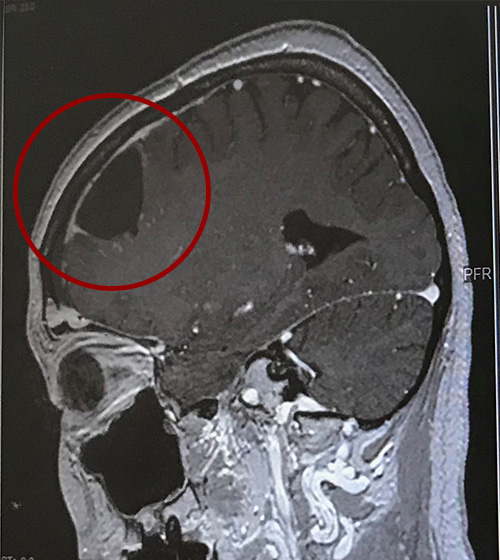

3ヶ月置きに岡山へ帰省し採血とMRI検査(レントゲン)をしていますが、今年の8月で術後丸3年経つとは思えないほど再発の様子が見られずとても良い経過とおっしゃっていただいていて、家族も私もほっとしています。

2021年1月15日:退院後3ヶ月経ったので、改めて造影MRIを撮影。→結果:悪性部分が増えている様子は無く、経過は順調♪

さて、タローは左前頭葉に特大7cm脳腫瘍が出来ていたので、摘出手術の際に「言語関係の運動神経を傷付ける可能性があり(最大限傷付けないようにする前提)、もしかすると術後はうまく言葉が出ないかもしれない」と言われていました。が、一切の後遺症も言語障害も無く麻痺も出なかったので、元気が故に院内を動き回る闘病ブロガーへ。。年齢が若いのもありますが、手術を無事成功させてくださった病院の皆さまに感謝感謝です。